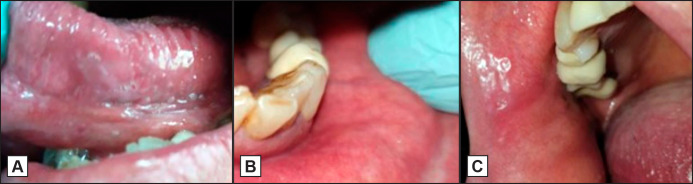

Results: Clinical examination revealed multiple aphthous-like ulcers on the ventral surface and lateral borders of the tongue, lower lip and mucolabial fold, buccal mucosa and soft palate. Dexamethasone oral solution 0.5 mg/5 ml was topically administered t.i.d. along with tramadol 50 mg per os t.i.d. for pain management. One week later, the pain was relieved and the ulcers were almost completely healed. Tramadol administration was discontinued and dexamethasone was tapered during the following 8 days. There was no need for discontinuation of panitumumab. In close follow-up for the next four months, no painful oral symptomatology was reported.